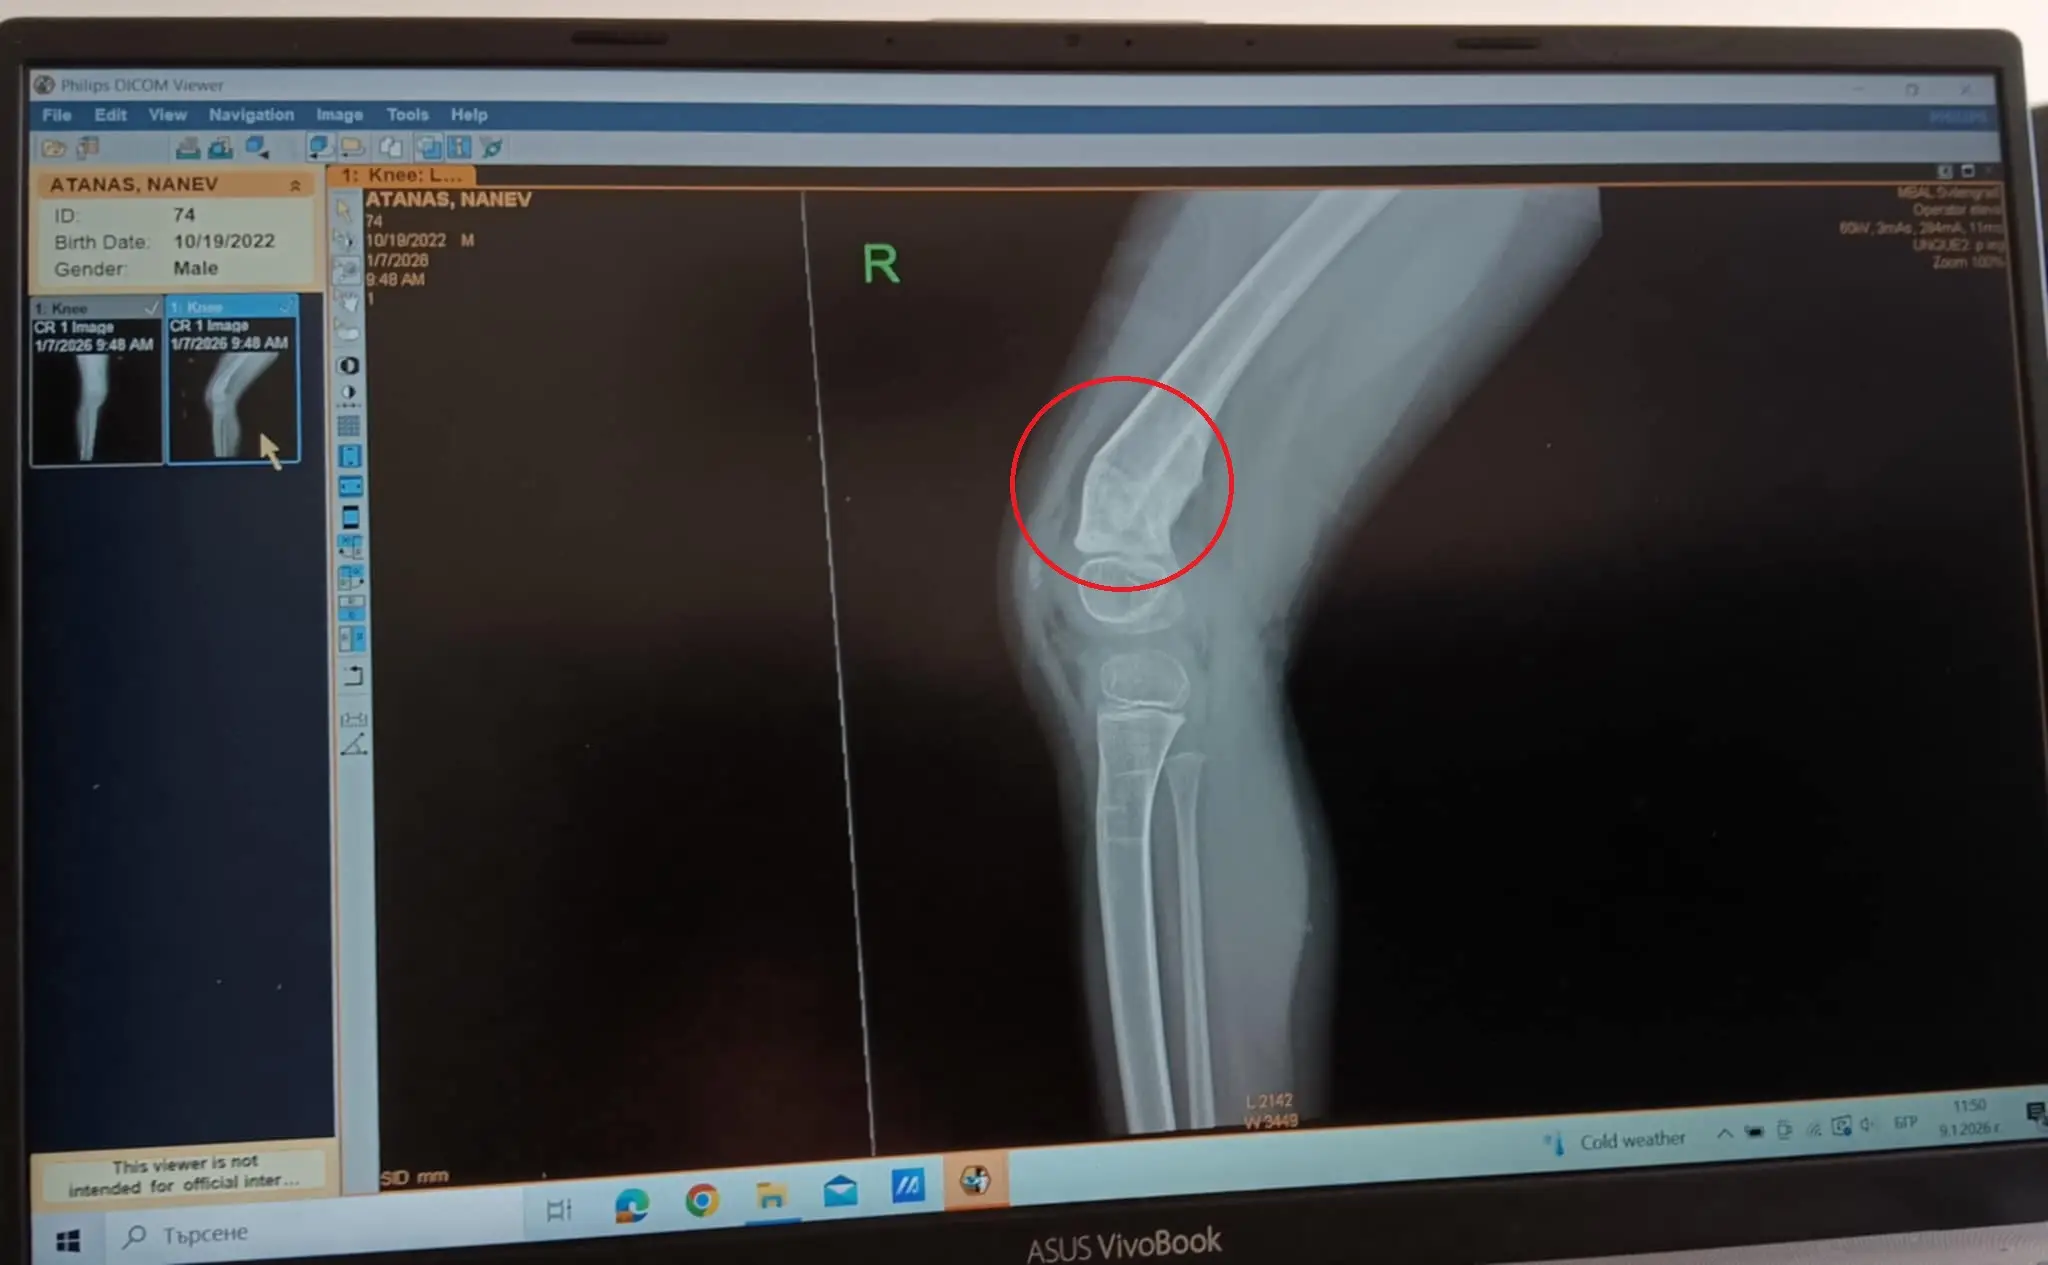

На 11.03.2025г. Атанас заедно с цялото му семейство претърпяха тежка катастрофа. Най - пострадал от произшествието беше именно Наско. Той беше приет в УМБАЛ "Св. Георги"  гр. Пловдив . След направени 2 скенера, изследвания и прегледи от специалисти, изписват Наско с леки фрактури в лицевата част и натъртвания. По време на 2-седмичния престой в болницата майката на Наско забелязва, че при докосване или движение на крачето детето плаче от болка, но лекарите не взимат отношение. В продължение на около месец Наско продължава да изпитва болка и майка му отново посещава Ортопед, който също отрича детето да има някаква травма. На втория месец след катастрофата посещават Ортопед в Турция. След направена снимка се оказва, че детето е било със счупена кост в областта на коляното, която е зарастнала леко накриво. Ортопедът дава надежда, че след интензивни рехабилитации болката ще изчезне и няма да е нужна оперативна намеса. Рехабилитаторите, които работят с Атанас, също са запознати със случая и работят усърдно той да започне да ходи самостоятелно.